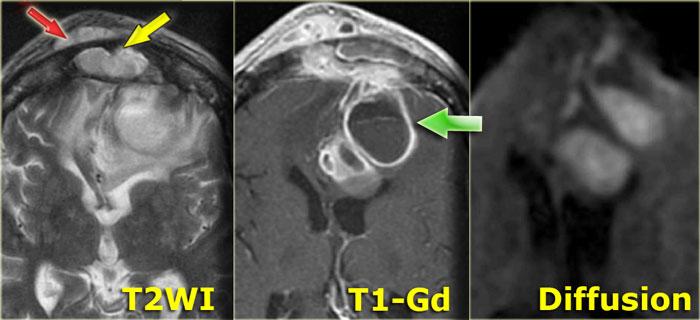

Áp xe não

Hình ảnh bên trái của một bệnh nhân ban đầu được chẩn đoán là u nguyên bào thần kinh đệm đa dạng (glioblastoma multiforme).

Có các bất thường ở cả hai thùy trán.

Tuy nhiên, hãy chú ý đến mô bất thường trong xoang trán (mũi tên vàng), áp xe dưới màng xương (mũi tên đỏ) và mức dịch-dịch (mũi tên xanh lá) trong tổn thương nội sọ lớn có hình ảnh ngấm thuốc dạng vòng nhẫn.

Tất cả các bất thường liên tục với nhau, cho thấy có sự phá hủy xương trán.

Hình ảnh khuếch tán hạn chế cũng hỗ trợ chẩn đoán áp xe não.

Đây là áp xe dưới màng xương và viêm tủy xương của xương trán, thường kèm theo sưng nề mềm và đau vùng trán.

Tình trạng này còn được gọi là khối u phồng Pott (Pott’s puffy tumor) theo tên Sir Pott, một phẫu thuật viên người Anh, người đầu tiên mô tả thực thể bệnh lý này.